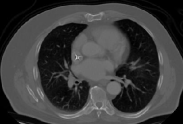

4.1.5 Chest CT

Chest CT scans play a relevant role in diagnosing a wide range of thoracic diseases, from infections to malignancies. By analyzing those scans, it is possible to detect diseases in the chest region, including pneumonia and cancer. The selected chest CT dataset 555https://www.kaggle.com/datasets/mohamedhanyyy/chest-ctscan-images contains 967 images across normal and three cancer types: adenocarcinoma, large-cell carcinoma, and squamous-cell carcinoma. Figure 6 provides a visual representation of the four highlighted classes.